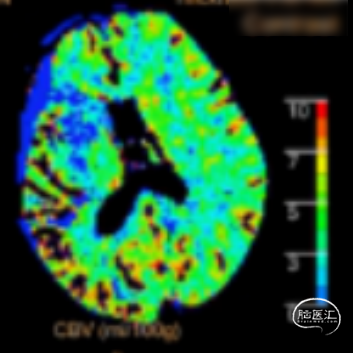

术前CTA+CTP示:1.右侧大脑中动脉M1段闭塞,前交通开放,右侧后交通开放;2.右侧大脑中动脉供血区大面积TTP、MTT延长,CBF降低,CBV减低。